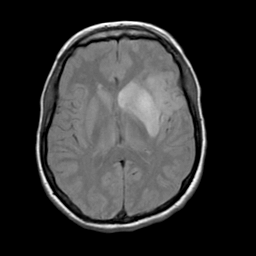

Acute Stroke: proton density-weighted MR -- Slice #14

[Home][Help][Clinical][Tour 1] Slice 14